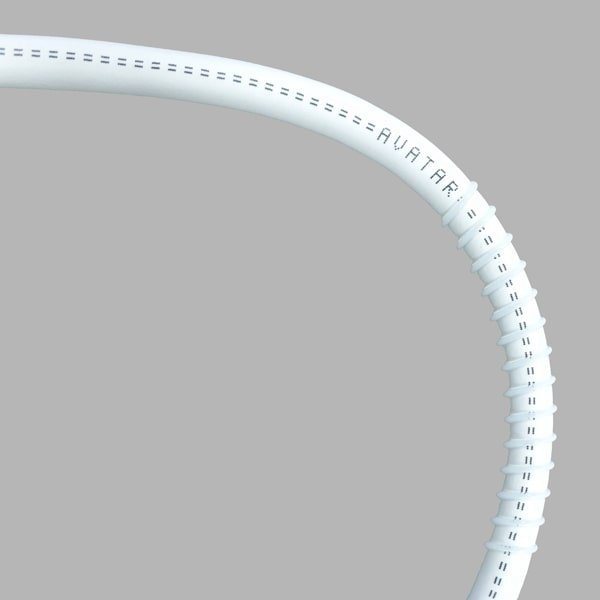

AVATAR PTFE Vascular Graft

AVATAR® PTFE Vascular Grafts are made entirely from PTFE. The AVATAR® graft does not have an external wrap but instead has an open pore structure averaging 20 microns internodal distance, encouraging tissue ingrowth and making it soft and easy to suture.

AVATAR PTFE Vascular Graft

AVATAR® PTFE Vascular Grafts are made entirely from PTFE. The AVATAR® graft does not have an external wrap but instead has an open pore structure averaging 20 microns internodal distance, encouraging tissue ingrowth and making it soft and easy to suture.

AVATAR® PTFE Vascular Grafts are made entirely from PTFE. The AVATAR® graft does not have an external wrap but instead has an open pore structure averaging 20 microns internodal distance, encouraging tissue ingrowth and making it soft and easy to suture. Helix grafts incorporate an external PTFE spiral support for use in applications where kink or crush resistance is required. Tapered and step tapered grafts can allow for better management of blood flow. All AVATAR® PTFE Vascular Grafts come sterile in dual barrier tray-within-tray packaging.